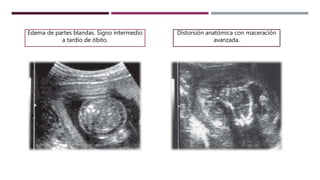

Edema de partes blandas. Signo intermedio

a tardío de óbito.

Distorsión anatómica con maceración

avanzada.